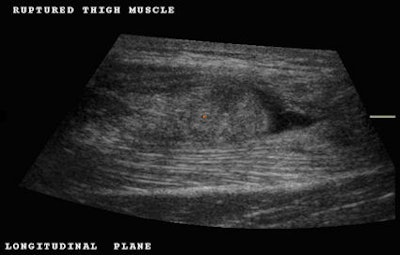

Initially, the examination of this patient was performed using traditional 2D ultrasound and subsequently with 3D ultrasound. Longitudinal scanning demonstrated the most distal portion of the rectus femoris muscle retracted with a swollen blunt end as a result of avulsion (Fig. 1). Active flexion of the thigh associated with extension of the leg causes the anterior mass to become more evident due to muscle contraction; this was observed in real-time ultrasound scanning. However, in order to permit patient comfort, 3D volume acquisition was performed with the patient in a relaxed position.

Fig. 1: Longitudinal plane demonstrating a distal aponeurosis tear. Note the retracted rounded end of the muscle and the presence of a distal hematoma (black area). All images courtesy of Dearbhla O'Dwyer and Dr. Stefano Ciatti.Once the location of the tear was determined, we decided to perform a 3D volume acquisition to better study the condition of the muscle and the full extent of the tear. Three-dimensional volume acquisition permits one to scroll backward and forward and up and down through the acquired volume.